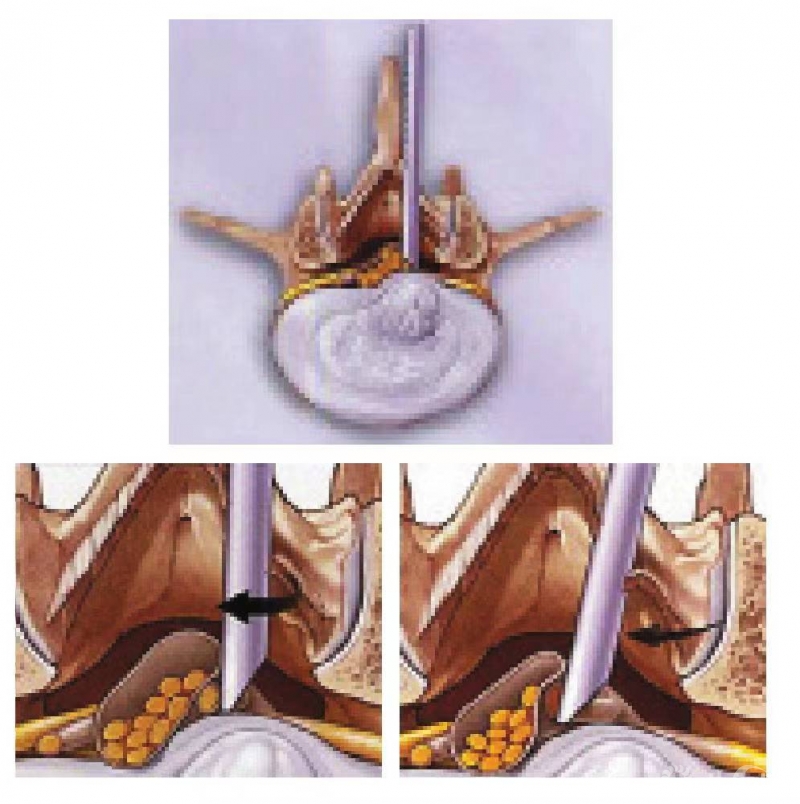

近十几年来,在脊柱内镜上有4项重大的改革,第一个就是Atony Yeung研发的脊柱内镜系统YESS,提供清晰的影像使手术能更清楚地进行,但Atony Yeung技术属于所谓的inside out技术(图1),即到椎间盘里掏出游离的碎片,属于间接性地减压,不能直接处理突出的椎间盘,事实上它的成功率<70%,大约在2001—2002年间徐少克医院已停用此类手术。

图1 切除椎间盘的从内到外的技术